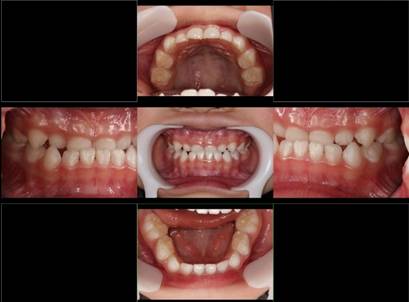

インビザGOによる矯正症例1 16歳男性

マウスピース矯正開始前。右上犬歯が内側にありました

前から見たところ

4か月後。犬歯が外側に出てきました

治療終了後10か月